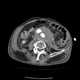

Retroperitoneal rupture of rectum